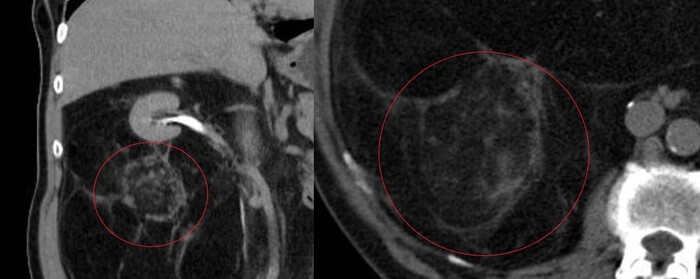

Было проведено КТ-обследование органов брюшной полости, где обращало на себя внимание необъятное объёмное жиросодержащее образование в забрюшинном пространстве с эпицентром справа, заполняющее собо практически весь живот:

Образование (красным) охватывало со всех сторон правую почку (голубым):

И имело солидный компонент:

Признаков инвазии (прорастания) в окружающие органы не было.

Согласно радиологической картине был выставлен предварительный диагноз забрюшинной липосаркомы.

Больной успешно прооперирован, образование удалено полностью, но правую почку спасти не удалось (она была полностью окружена опухолью, посему пришлось удалять комплексом).

Гистологический диагноз: высокодифференцированная забрюшинная липосаркома.